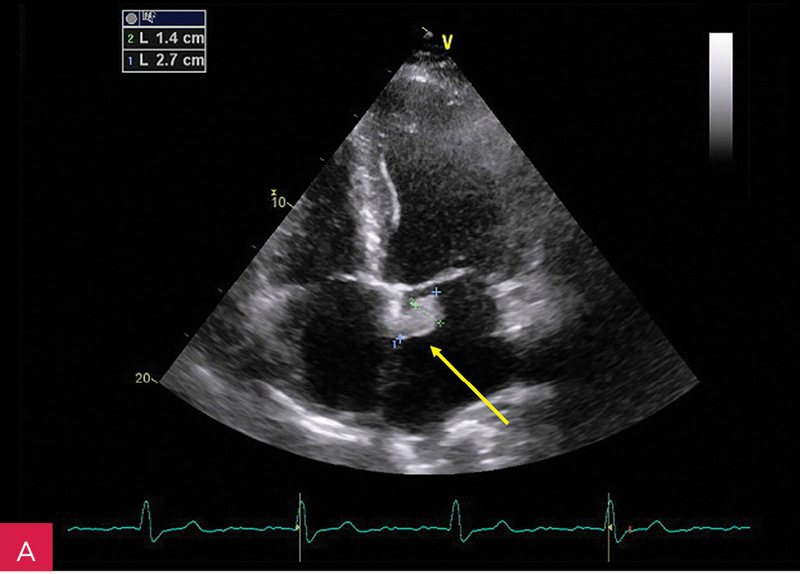

W badaniu echokardiograficznym przezklatkowym (TTE – transthoracic echocardiography) uwidoczniono guzowatą zmianę o wymiarach 37 × 28 × 25 mm u podstawy tylnego płatka zastawki mitralnej i w obrębie ściany dolno-bocznej lewej komory, o nierównej powierzchni od strony komory, nieznacznej ruchomości zgodnej z ruchem serca i niejednorodnej echostrukturze ze zwapnieniami (ryc. 2-5). Powodowała ona niewielkie ograniczenie ruchomości płatków zastawki mitralnej z utrudnieniem napełniania komory i parametrami małej stenozy (ryc. 6). Stwierdzono ponadto małą niedomykalność mitralną (ryc. 6), dużą niedomykalność trójdzielną, znacznie powiększone obydwa przedsionki oraz w niewielkim stopniu prawą komorę w zakresie drogi odpływu, a także niewielki przerost ścian lewej komory. W badaniu nie stwierdzono wyraźnych odcinkowych zaburzeń kurczliwości lewej komory. Globalna funkcja skurczowa lewej i prawej komory była zachowana w dolnych granicach normy: frakcja wyrzutowa lewej komory (LVEF – left ventricular ejection fraction) 50%, skurczowe przemieszczenie płaszczyzny pierścienia trójdzielnego (TAPSE – tricuspid annular plane systolic excursion) 18 mm. Stwierdzono cechy dysfunkcji rozkurczowej lewej komory z cechami wysokiego ciśnienia napełniania. Zarejestrowano również małą ilość płynu w osierdziu (do 6 mm za ścianą boczną lewej komory).

Rycina 7A-D. Obrazy rezonansu magnetycznego w osi krótkiej na wysokości pierścienia mitralnego: czarnej krwi T1-zależne TSE (A); czarnej krwi T2-zależne HASTE (B); T1-zależne echa gradientowego dynamicznie podczas podawania środka kontrastowego (C); sekwencja SSFP, pojedynczy obraz w osi krótkiej (D). W dolno-bocznej części pierścienia mitralnego od strony światła lewej komory zmiana (strzałki) niskosygnałowa we wszystkich ważeniach sygnału

W celu weryfikacji zmiany i oceny charakterystyki tkanki wykonano CMR,

w którym stwierdzono w dolno-bocznej części pierścienia mitralnego od strony światła lewej komory zmianę odpowiadającą morfologicznie CCMA, obejmującą 7,3 cm obwodu pierścienia mitralnego, o grubości w osi krótkiej do 25 mm, w osi długiej do 21 mm; zmiana ulegała brzeżnemu wzmocnieniu kontrastowemu i powodowała ograniczenie ruchomości tylnego płatka zastawki mitralnej, obejmowała struny ścięgniste mięśnia brodawkowatego tylno-przyśrodkowego. Ponadto uwidoczniono znacznie powiększone przedsionki z istotnym włóknieniem – jak w restrykcji (ryc. 7, 8).